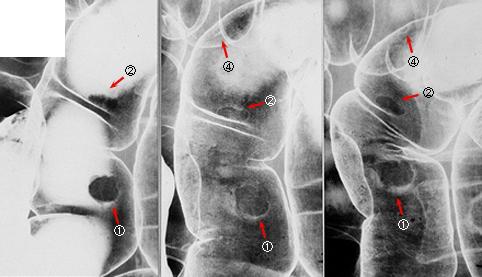

疾患(病理主体)の分類良性上皮性腫瘍/腺腫

部位(臓器別)大腸/S状

検査方法X-P

病変の最大径(ミリ)10〜14